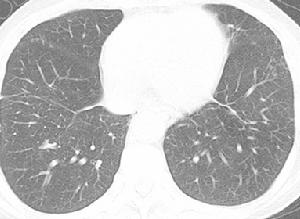

1.微粒栓塞治療巨塊型肝癌伴雙肺多發轉移